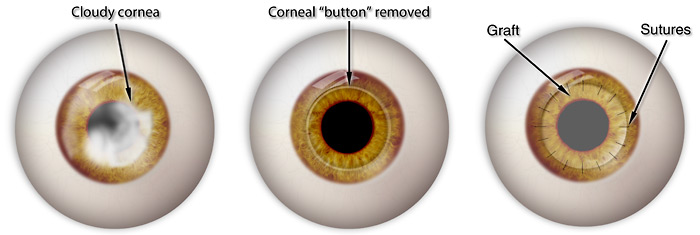

– Transplantes de córnea: Última opção nos Casos Avançados

O transplante de córnea é reservado para os casos mais avançados de ceratocone — quando há cicatrizes corneanas, opacidades centrais, quando a deformidade e o afinamento da córnea são tão intensos que impedem qualquer reabilitação visual com lentes de contato, anel intraestromal ou outras intervenções menos invasivas.

Existem dois tipos principais de transplante utilizados no tratamento do ceratocone:

1. DALK (Deep Anterior Lamellar Keratoplasty)

É um transplante parcial que substitui as camadas anteriores da córnea, preservando o endotélio (camada interna). Essa técnica tem a vantagem de apresentar menor risco de rejeição, uma vez que a parte mais imunologicamente sensível do olho permanece intacta. É a cirurgia ideal para casos em que o endotélio está preservado — o que ocorre na maioria dos ceratocones, mesmo em fases avançadas.

2. Transplante penetrante (PK – Penetrating Keratoplasty)

Neste procedimento, todas as camadas da córnea são substituídas. É indicado quando há cicatrizes profundas, opacidades centrais ou falha prévia de um transplante lamelar. Embora seja eficaz, o transplante penetrante tem maior risco de rejeição e complicações como infecção, descompensação do enxerto e astigmatismo elevado no pós-operatório.

Complicações e Durabilidade dos transplantes

Apesar de seguros quando bem indicados, os transplantes de córnea são procedimentos de maior complexidade e apresentam riscos que precisam ser considerados:

- Rejeição imunológica do enxerto;

- Infecções pós-operatórias;

- Astigmatismo irregular significativo;

- Falência do transplante com o passar dos anos.

A duração média de um transplante de córnea varia de 10 a 15 anos, podendo variar conforme o tipo de cirurgia, resposta individual do paciente e cuidados pós-operatórios. Após esse período, pode haver necessidade de um novo procedimento.

Por isso, os transplantes são sempre considerados a última alternativa terapêutica, usados apenas quando todas as demais opções foram esgotadas. A boa notícia é que, com diagnóstico precoce e acompanhamento adequado, é possível evitar essa etapa na grande maioria dos casos.